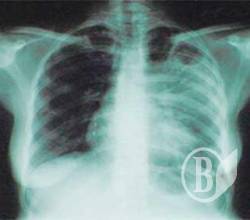

Самой распространённой формой был активный туберкулёз лёгких. С диагнозом этой болезни в прошлом году зарегистрировано 833 больных против 755 в 2007г.